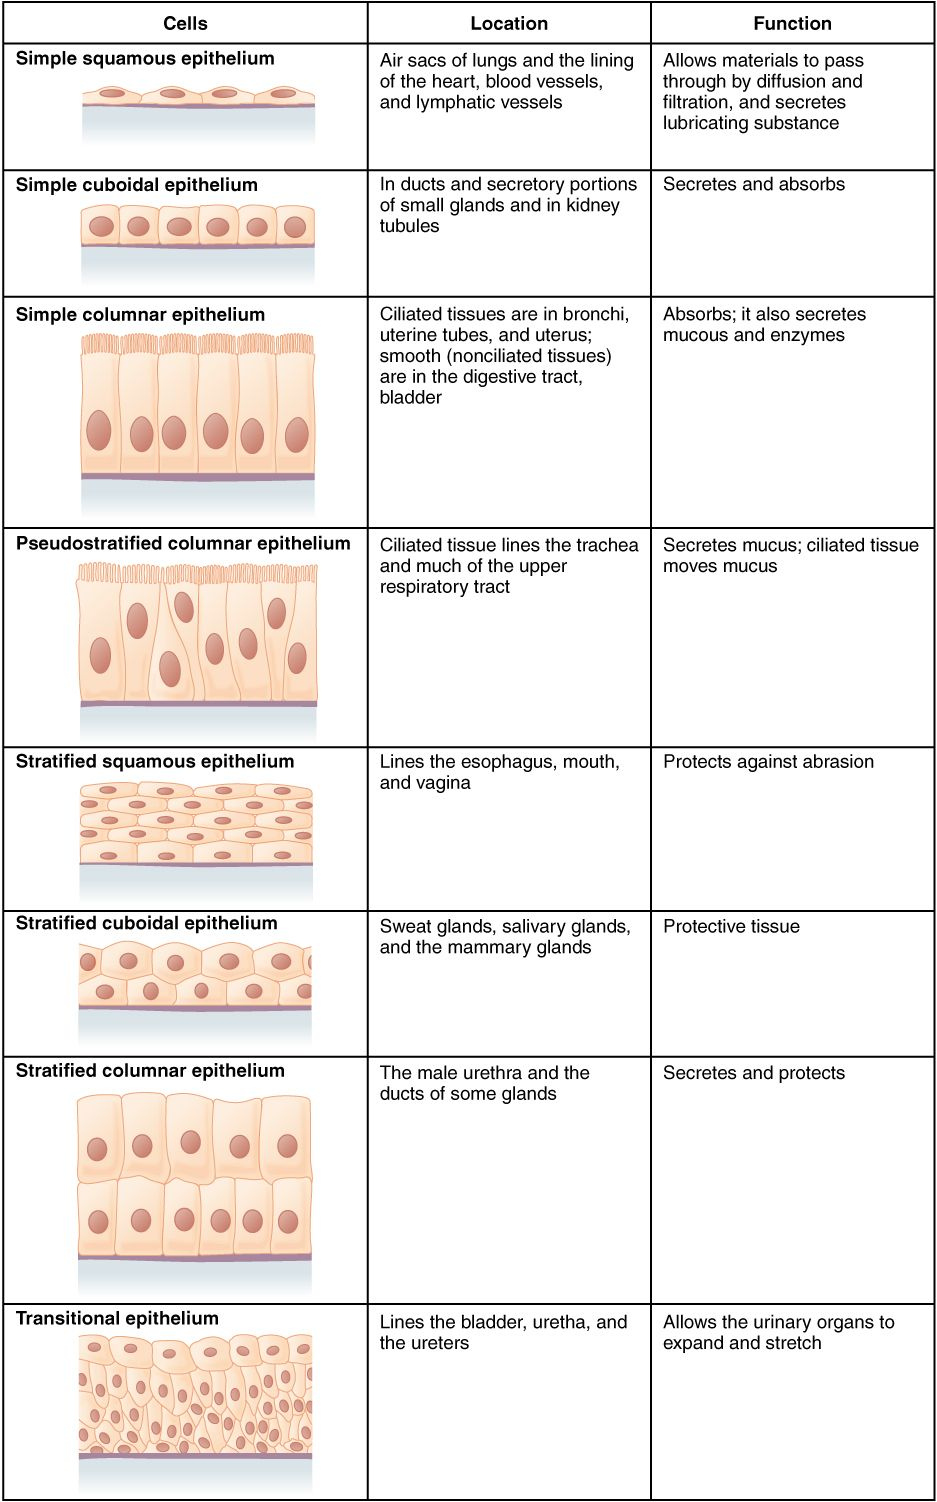

Anatomy worksheets help you learn the anatomy of various organs. You can additionally discover regarding the mitral shutoff, which shields the opening in between the left atrium as well as the ventricle.

Anatomy worksheets are additionally useful for students to find out regarding the heart. They can learn the functions of heart muscle mass and also exactly how they affect the heart’s output.

Anatomy worksheets come in a selection of formats, consisting of shade and classified variations. They are developed for elementary school trainees. These printable worksheets are terrific for students, teachers, and also those thinking about natural wellness, physiotherapy, and massage therapy.

For a fun way to enhance discovering regarding the human body, you can make use of Anatomy and Physiology Blood Vessels Worksheet. Some of them have labels to make it easy to identify parts of the body.